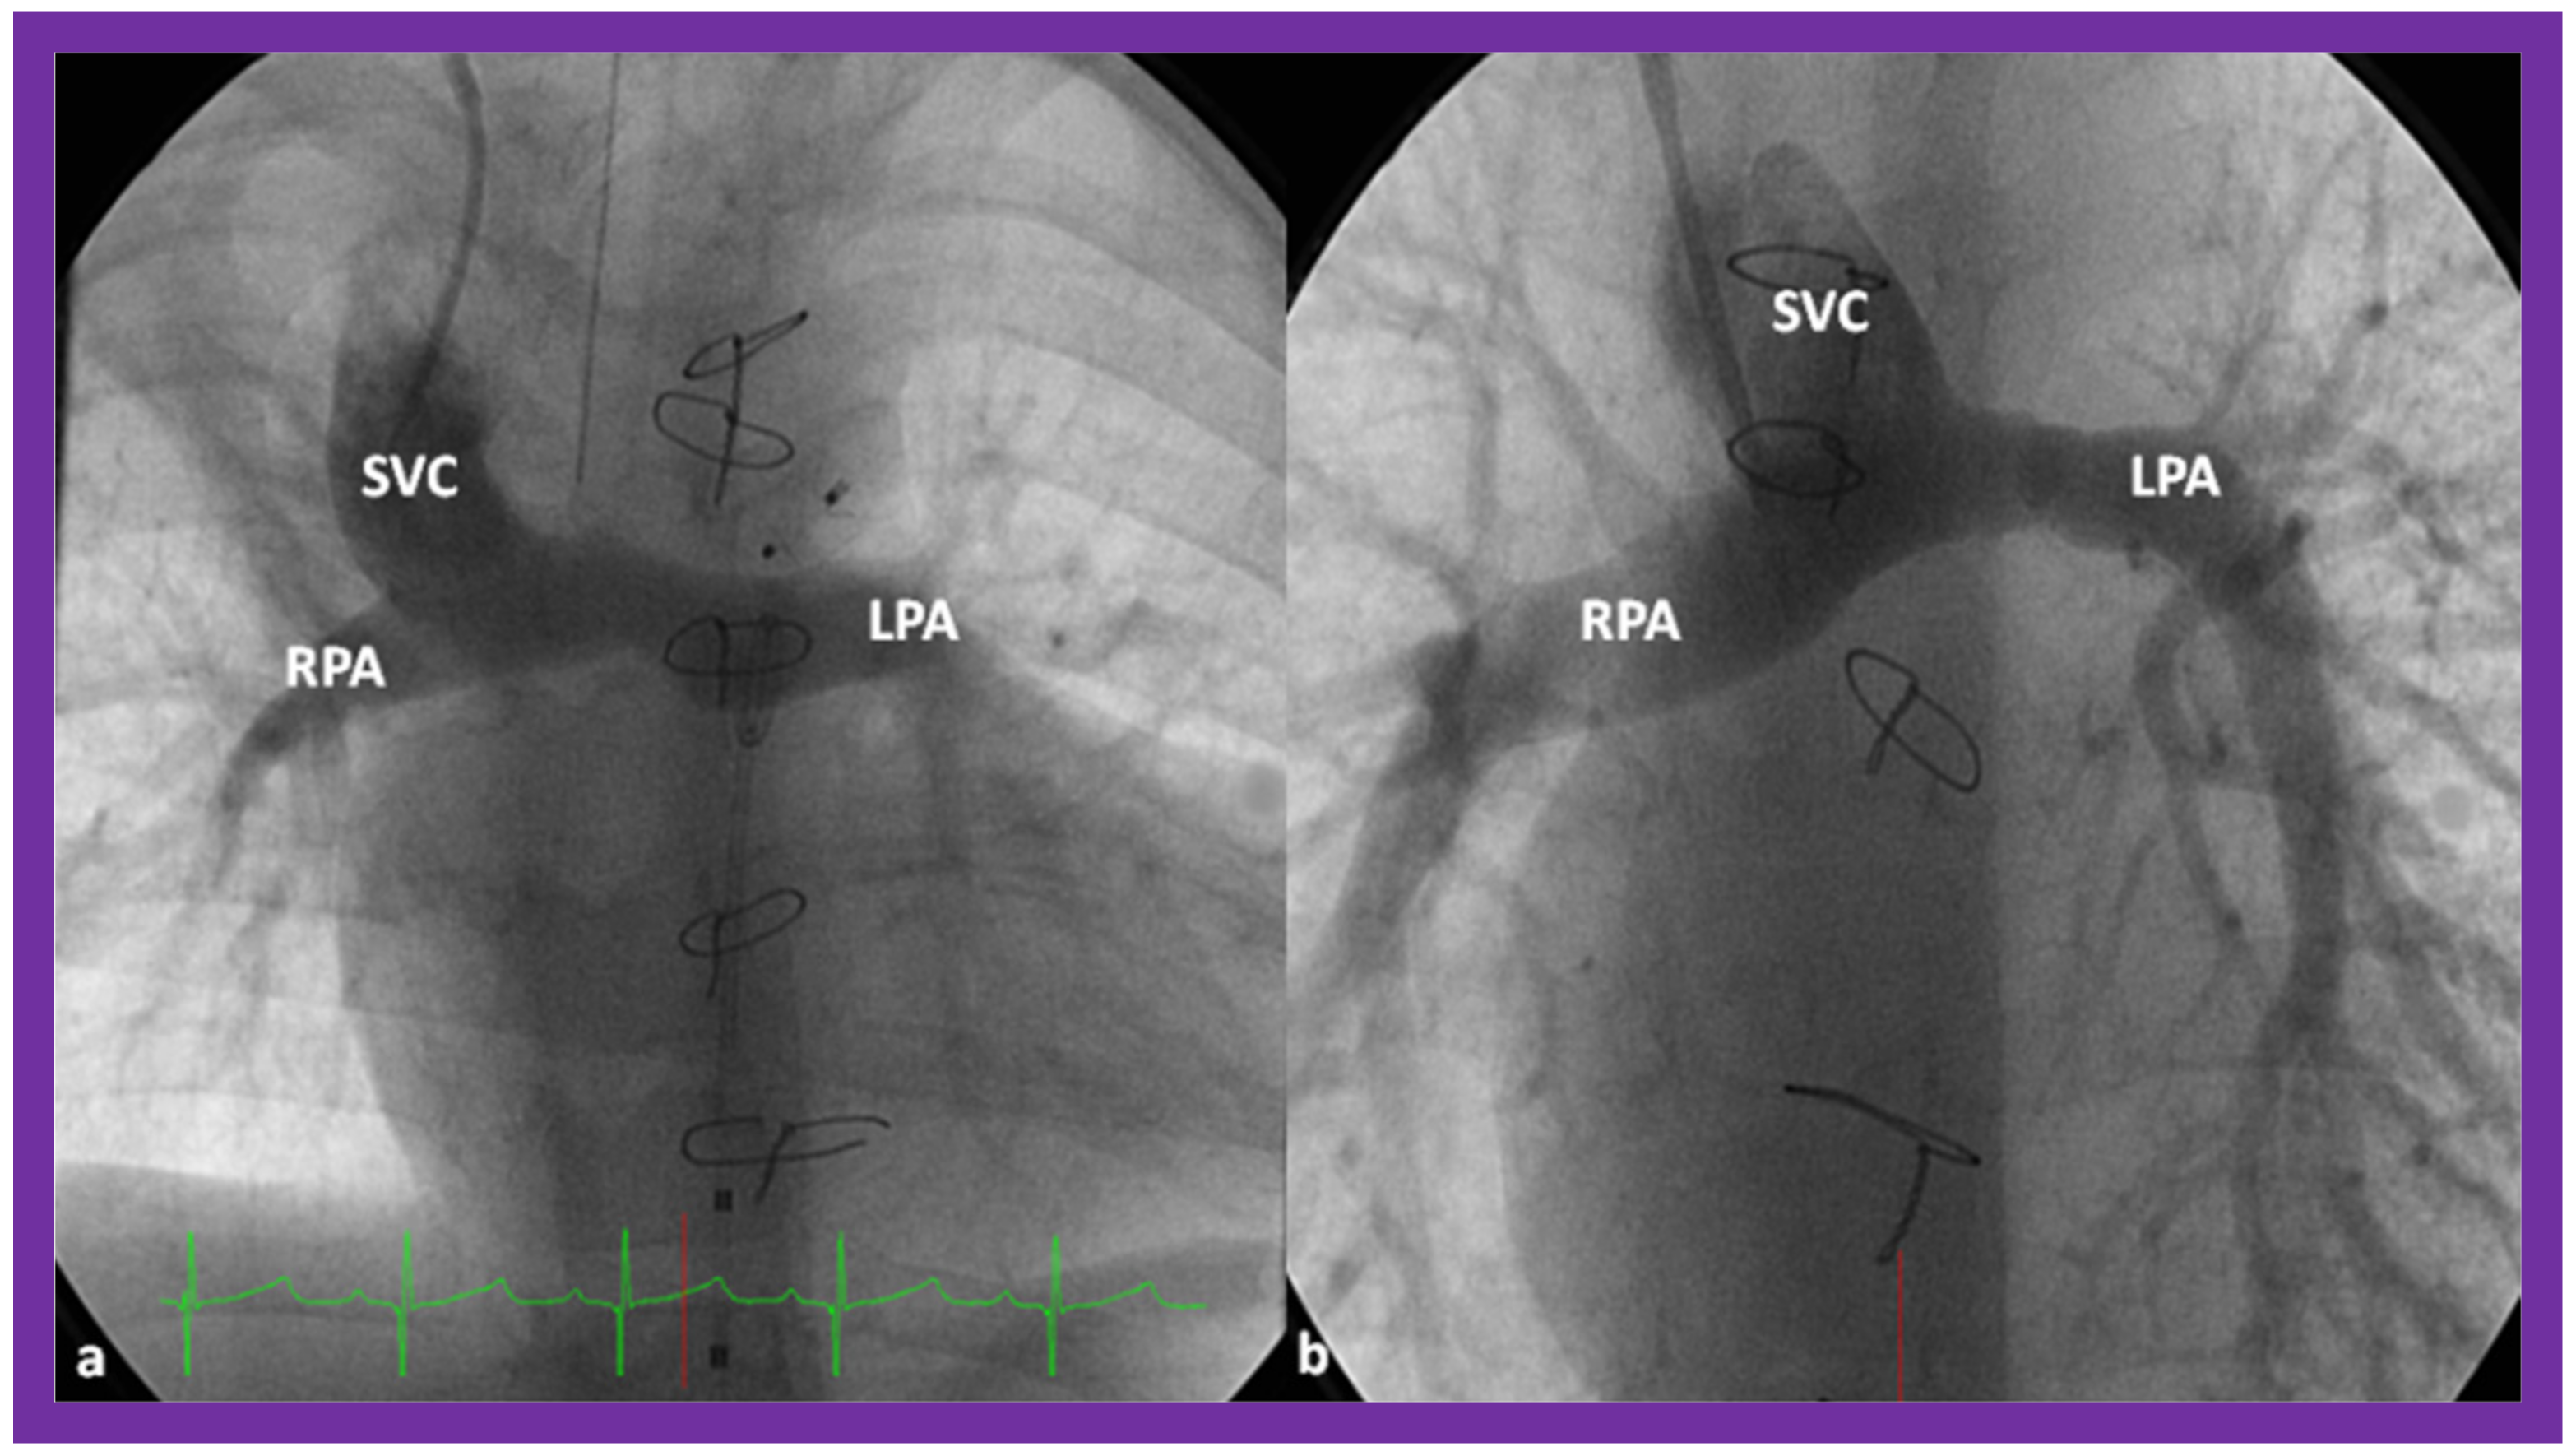

7. Echocardiogram

10.2. Stage II